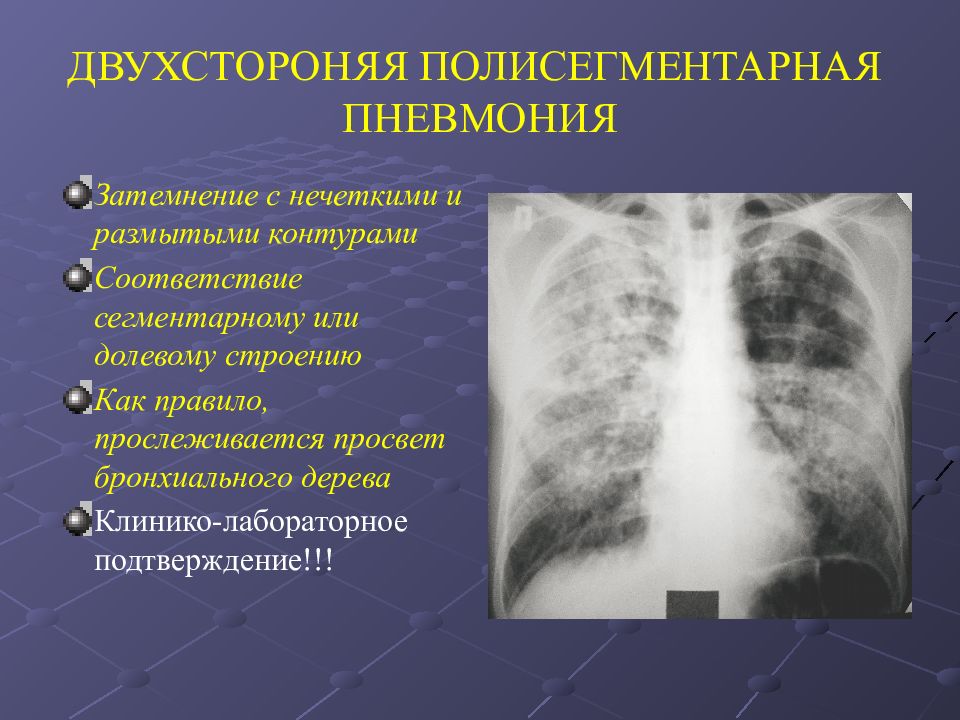

Рентгеновские снимки при врожденной эмфиземе легкого

Раздел: Визуальные уроки